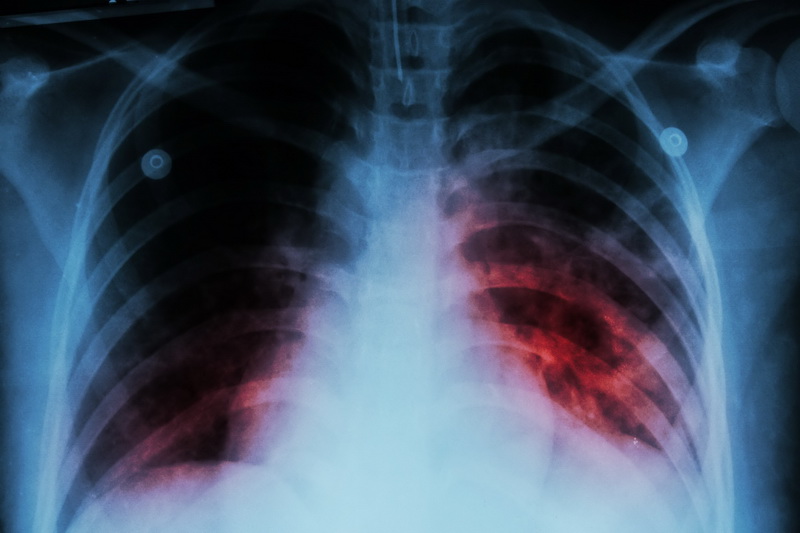

Nakon COVID-19, tuberkuloza je najsmrtonosnija zarazna bolest na svijetu. Uzrokuju ga bakterije koje obično pogađaju pluća. Klice se uglavnom prenose s osobe na osobu u zraku, na primjer kada zaražena osoba kašlje ili kiše.

Iako je moguće liječiti zahvaljujući naučnim istraživanjima, tuberkuloza i dalje svake godine uzima veliki broj života širom svijeta.